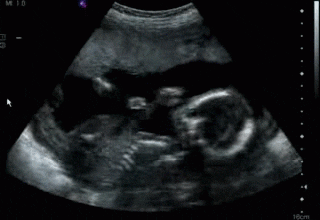

在孕5~6周,通过超声检查可以根据宫内孕囊的数目初步判断是否为单胎或者双胎。

一般来说宫腔内如果有两个孕囊,同时存在两个卵黄囊或者胎芽胎心,即初步判断为双卵双胎,如果只看到一个孕囊,其内存在两个卵黄囊或者胎芽胎心,即单卵双胎。

异期怀孕或者同期怀孕就是通过超声的检查,推算受孕的时间后确定的。早孕期同期怀孕的胎儿大小基本相同,异期怀孕的胎儿大小相差甚远。

总的来说,超声在多胎妊娠中有着重要的作用,孕早期帮助我们识别是不是多胎妊娠,以及核对每个胎儿的孕周,在怀孕过程中,我们也可以通过超声监测,了解胚胎是否正常生长,有没有出现生长受限或者胎死宫内等异常。